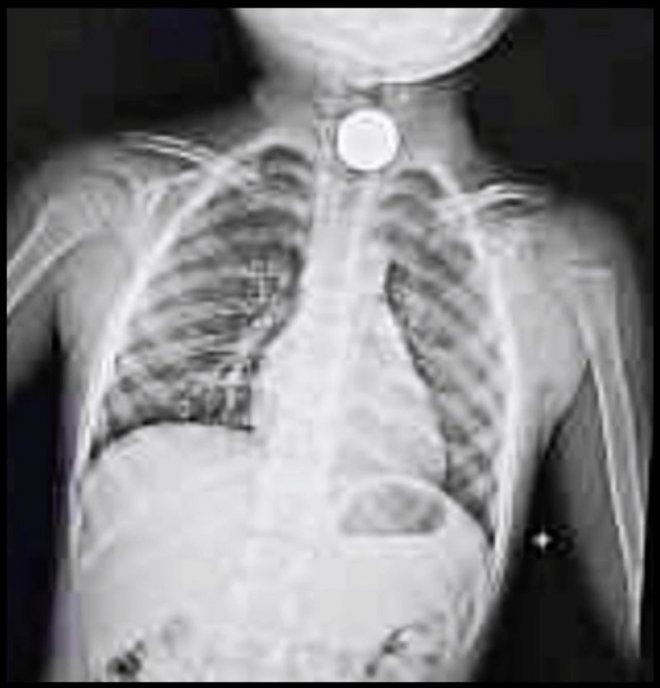

羅文裕表示,兒子在午睡30分鐘後,突然放聲大哭,同時大喊,「有錢錢卡在喉嚨,很痛」。他馬上伸出手指到喉嚨內尋找,同時拍背安撫,但一直沒有找到異物。奇怪的是,兒子仍相當痛苦,焦急的他立刻將孩子送到急診室檢查。當時,兒子疑似因為過於緊張,在院內吐了一地,但也沒有找到他口中的「錢錢」,認為應該已經脫離險境,但為求保險仍拍攝X光片確認。

未料,檢查結果出爐後,發現兒子食道處真的有一塊5元硬幣,讓他大驚失色,連忙幫孩子轉至大醫院求診。醫師確認無誤後,表示要進行全身麻醉,使用專業儀器取出,「中間抽血、內視鏡檢查這些哀嚎、爹娘心疼落淚的過程在此就快轉帶過」。終於,在8小時的處理後,硬幣才被順利取出,結束一場虛驚。